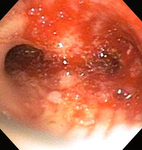

Bronchoscopic therapy for central airway obstruction of the right mainstem: post-mechanical debulking

From the collections of Jose Fernando Santacruz MD, FCCP, DAABIP and Erik Folch MD, MSc; used with permission